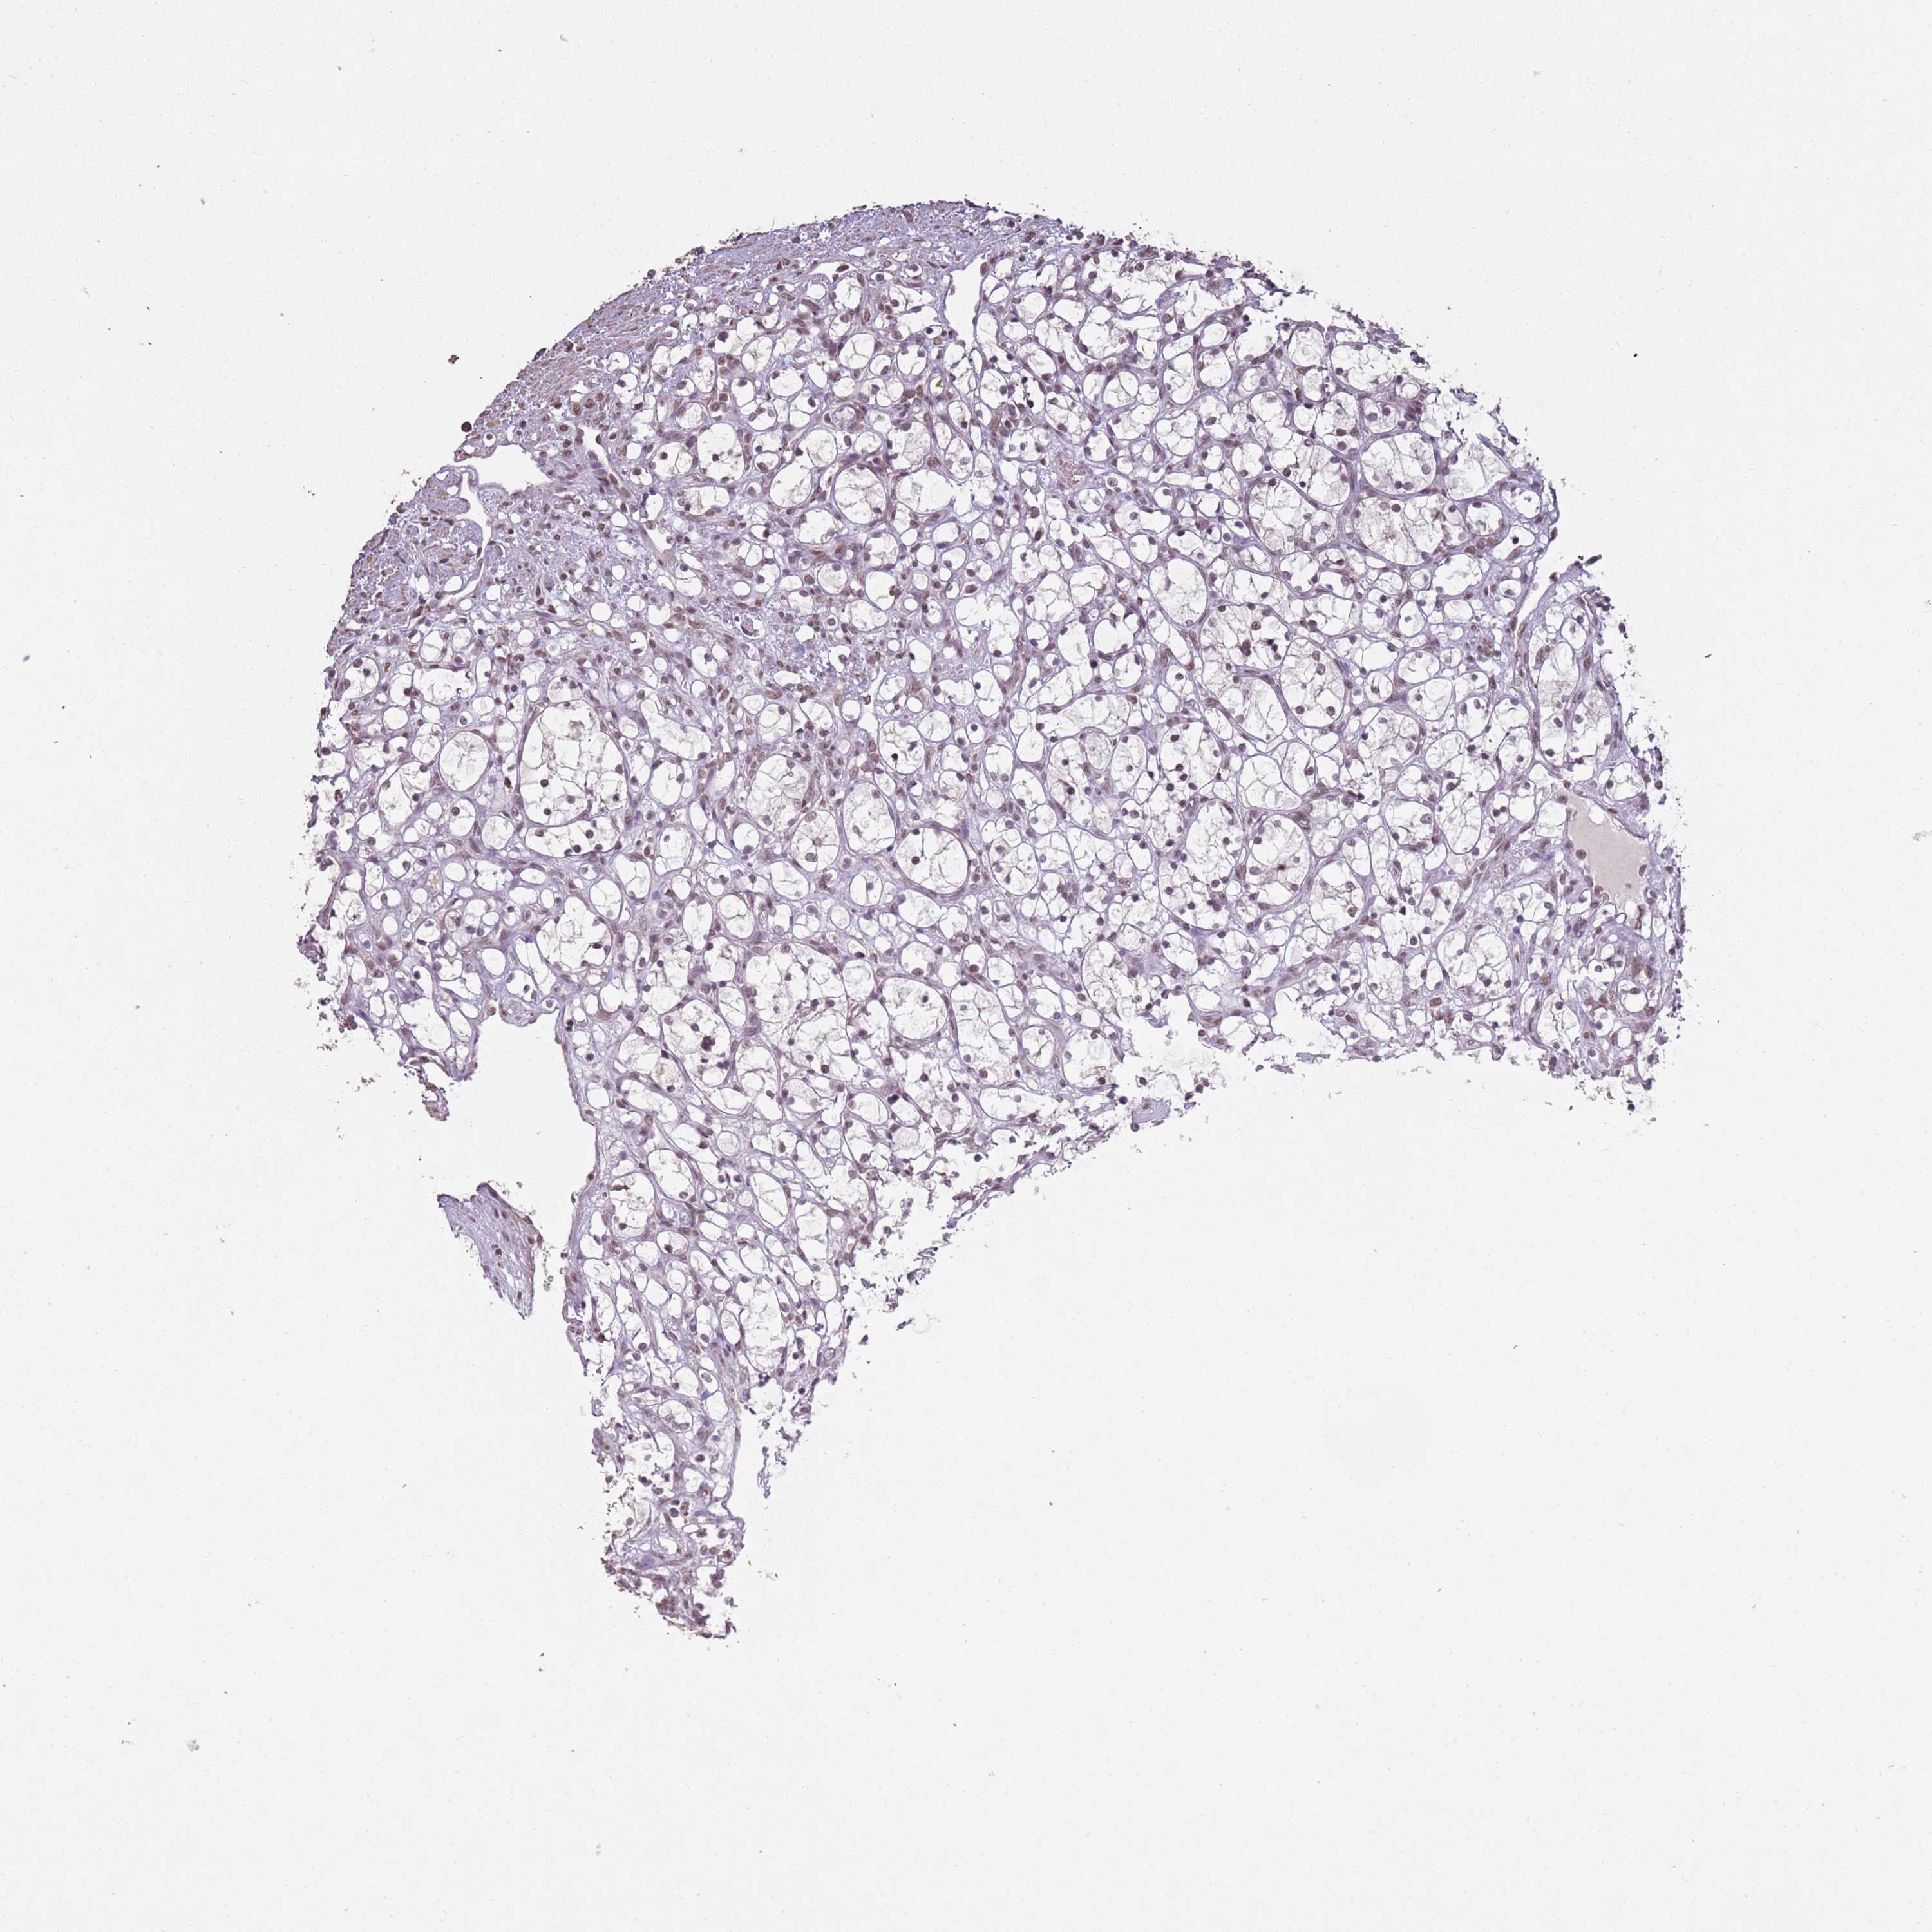

KIDNEY RENAL CLEAR CELL CARCINOMA (VALIDATION) - Interactive survival scatter ploti

The Survival Scatter plot shows the clinical status (i.e. dead or alive) for all individuals in the patient cohort, based on the same data that underlies the corresponding Kaplan-Meier plots. Patients that are alive at last time for follow-up are shown in blue and patients who have died during the study are shown in red.

The x-axis shows the expression levels (FPKM) of the investigated gene in the tumor tissue at the time of diagnosis. The y-axis shows the follow-up time after diagnosis (years). Both axes are complimented with kernel density curves demonstrating the data density over the axes. The top density plot shows the expression levels (FPKM) distribution among dead (red) and alive patients (blue). The right density plot shows the data density of the survived years of dead patients with high and low expression levels respectively, stratified using the cutoff indicated by the vertical dashed line through the Survival Scatter plot. This cutoff is automatically defined based on the FPKM cutoff that minimizes the p-score. The cutoff can be changed by dragging the vertical line or by entering a cutoff value in the square labeled "Current cut-off".

Under the Survival Scatter plot the p-score landscape (black curve; left axis) is shown together with dead median separation (red curve; right axis). Dead median separation is the difference in median mRNA expression between patients who have died with high and low expression, respectively. It is calculated as follows: median FPKM expression of dead patients with high expression - median FPKM expression of dead patients with low expression. This is intended to aid the user in visually exploring custom cutoffs and the associated p-scores and dead median separation.

Individual patient data is displayed and can be filtered by clicking on one or more of the category buttons on the top of the page. Categories describing expression level and patient information include: high, low, alive, dead, female, male and tumor stages. The scale of the x-axis can be toggled between linear and log-scale by clicking on the "x log" button. Mouse-over function shows TCGA ID, patient information and mRNA expression (FPKM) for each patient.

& Survival analysisi

Kaplan-Meier plots summarize results from analysis of correlation between mRNA expression level and patient survival. Patients were divided based on level of expression into one of the two groups "low" (under cut off) or "high" (over cut off). X-axis shows time for survival (years) and y-axis shows the probability of survival, where 1.0 corresponds to 100 percent.

ARL14EP is validated prognostic, high expression is favorable in Kidney Renal Clear Cell Carcinoma (validation)

Best expression cut offi

Based on the FPKM value of each gene, patients were classified into two groups and association between prognosis (survival) and gene expression (FPKM) was examined. The best expression cut-off refers the FPKM value that yields maximal difference with regard to survival between the two groups at the lowest log-rank P-value. Best expression cut-off was selected based on survival analysis .

When clicking on this number, the vertical dashed line indicating cut-off, the interactive survival plot, and the Kaplan-Meier curve will be adjusted to show results based on the best expression cut-off.

: 16

TCGA RNA samplesi

RNA-seq data is reported as average FPKM (number Fragments Per Kilobase of exon per Million reads), generated by the The Cancer Genome Atlas (TCGA) .

Normal distribution across the dataset is visualized with box plots, shown as median and 25th and 75th percentiles. Points are displayed as outliers if they are above or below 1.5 times the interquartile range. FPKM values of the individual samples are presented next to the box plot.

Average pTPM 17.3

Number of samples 100